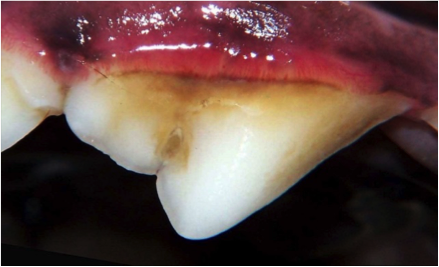

When rough tartar accumulates on tooth surfaces and touches the gum line it’s time for a professional oral assessment, treatment, and prevention visit. This visit will include a thorough dental examination, teeth cleaning, and polishing to remove the tartar and invisible plaque from all of the tooth surfaces.

After examination, tooth scaling will be performed, using both hand and ultrasonic scalers to remove tartar above and below the gum line. The tartar below the gum line causes the most significant periodontal disease, so it is important that it be thoroughly removed.